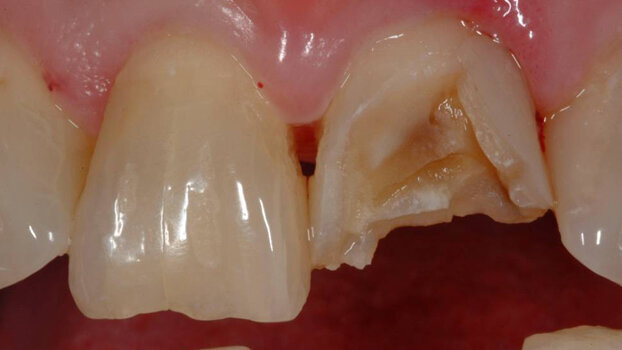

Dental injuries are the most common type of orofacial injury sustained during participation in sports. According to the National Youth Sports Foundation for Safety, in the United States, an estimated 5 million teeth are knocked out each year during sports activities.

Also, as the NBA examples support, almost all of these dental injuries involve the maxillary central incisors. A 2001 study by Gabris et al. found that 85-87 per cent of all dental injuries from sports involved tooth No. 8 and/or 9.